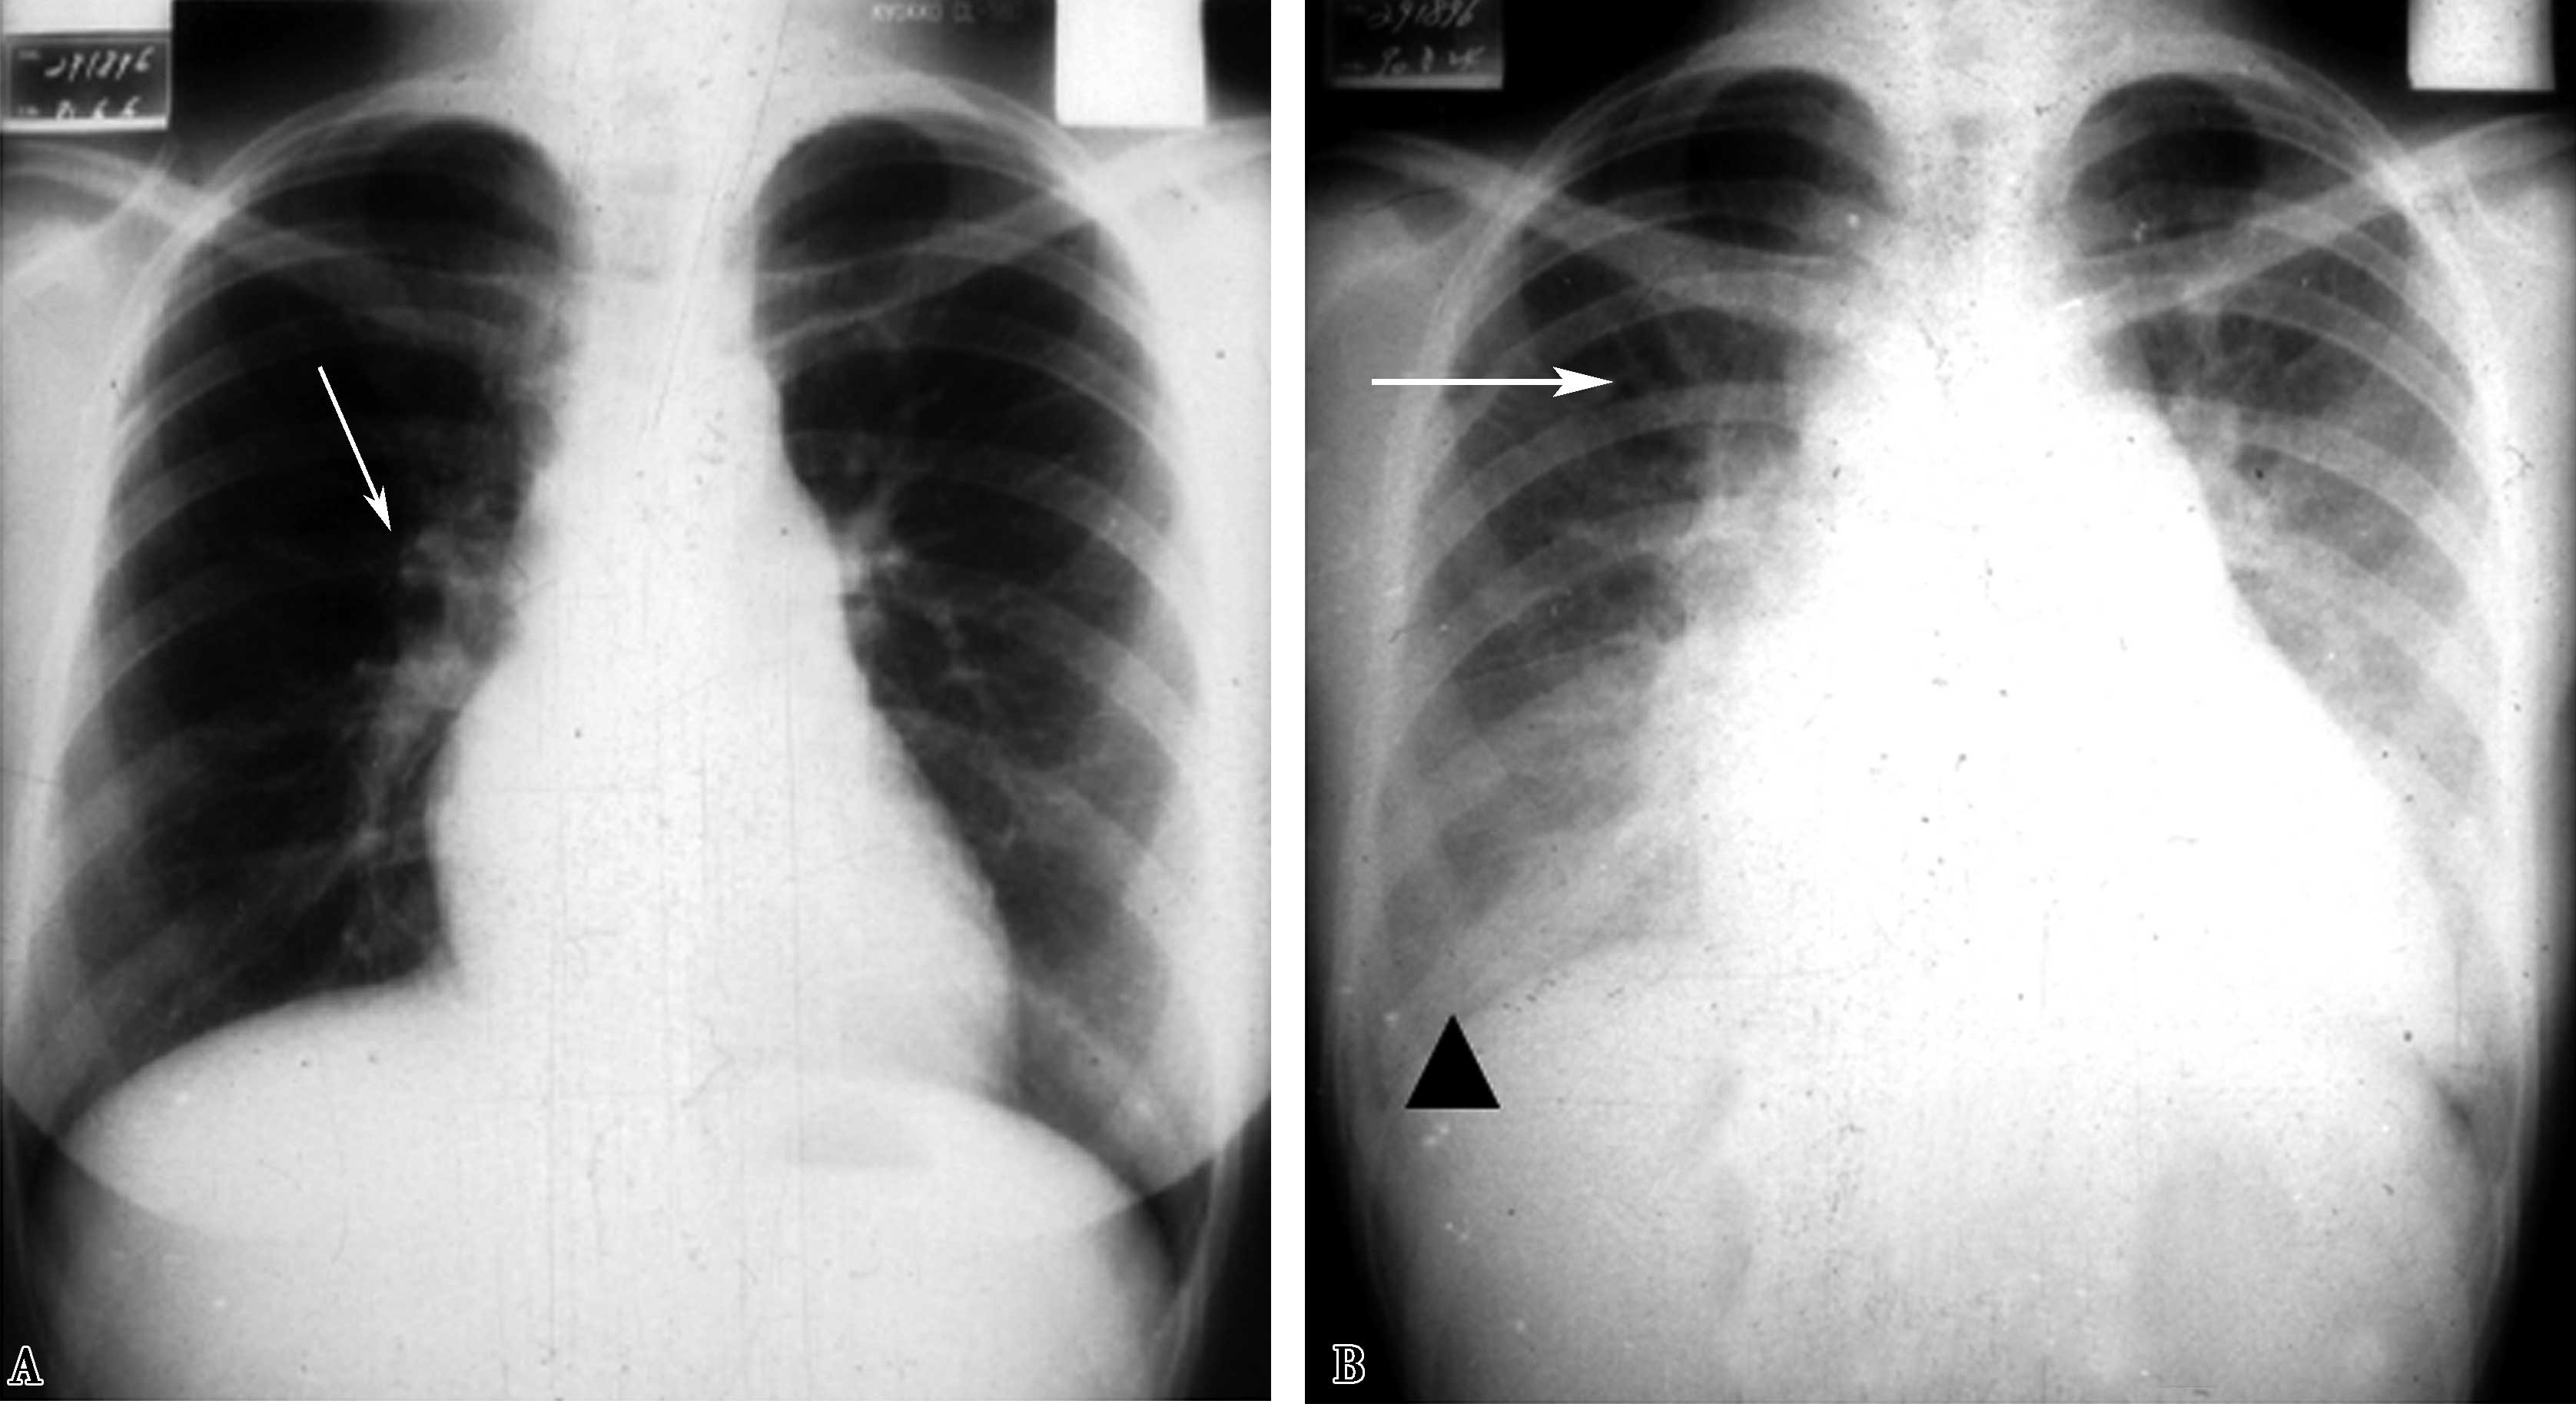

图7-2-9胸部正、侧位X线片示:两肺血多,肺动脉段凸,右下肺动脉增宽>1.5cm;右心室增大(肥厚为主)。X线片诊断:肺动脉高压,继发于左-右分流先天性心脏病。CTA证实为房间隔缺损(Ⅱ孔型)。

图7-2-9 男,39岁,劳累后气短,心电图:右心室肥厚;超声心动图:肺动脉高压,72mmHg

图7-2-11 男,38岁,慢性肺栓塞5年,超声测肺动脉压110mmHg。A.胸部正位两肺纹理分布不均,两下肺纹理稀少,右下肺动脉增宽呈截断现象,上肺动脉迂曲增宽;肺动脉段高度凸出(↑),右心房室增大;B.左侧位心前间隙缩小,肺动脉圆锥扩张(↑)。X线胸片诊断:慢性血栓栓塞性肺动脉高压

X线征象:肺淤血,左心房及右心室增大,肺循环高压(肺动脉高压+肺静脉高压)(图7-2-12)。

图7-2-12 男,36岁,二尖瓣狭窄,肺动脉高压。X线片,AB.两肺间质性肺水肿,肺动脉高压(右下肺动脉2.0mm↑),左心房、右心室增大(↑),诊断二尖瓣狭窄,肺循环高压(肺动脉及肺静脉高压);C.超声心动图:二尖瓣口面积:1.02cm 2 (↑);PAP:78mmHg